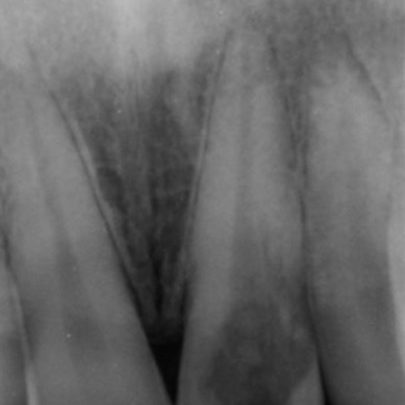

External cervical resorption typically presents as an asymmetrical radiolucency with irregular borders (Figure 4).

The outline of the root canal is visible through the lesion indicating the resorption is on the external aspect of the tooth.

The lesion may appear cloudier or mottled if it has progressed into a more reparative phase.

In addition to this, not all external cervical resorption lesions follow the ‘typical’ radiographic appearance mentioned above (Figure 5). A CBCT provides crucial information to obtain successful outcome.